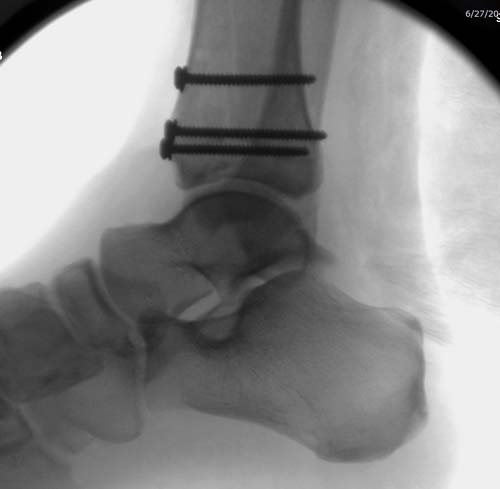

Второй случай в результате скоростной травмы, кроме пилона, вовлечение

других органов! Отек при поступлении и открытый перелом на другой

стороне. В таких случаях нет смысла спешить, и временный наружный

фиксатор на несколько дней. После спадения отека фиксация

передне-наружной пластиной.  Реабилитация - ранние движения, без

нагрузки.